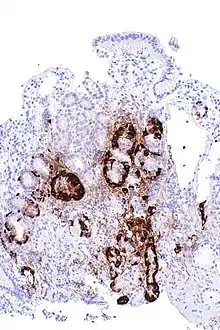

Micrograph showing nodular enterochromaffin-like cell hyperplasia, as demonstrated with chromogranin A immunostaining, in the body of the stomach. Parietal cells are not readily apparent. These changes are in keeping with autoimmune metaplastic atrophic gastritis, a histologic correlate of vitamin B12 deficiency anemia.

PA may be considered as an end stage of autoimmune atrophic gastritis, a disease characterised by stomach atrophy and the presence of antibodies to parietal cells and intrinsic factor.[36][37] Autoimmune atrophic gastritis, is localised to the body of the stomach, where parietal cells are located.[34] Antibodies to intrinsic factor and parietal cells cause the destruction of the oxyntic gastric mucosa, in which the parietal cells are located, leading to the subsequent loss of intrinsic factor synthesis. Without intrinsic factor, the ileum can no longer absorb the B12.[38] Atrophic gastritis is often a precursor to gastric cancer.[37]